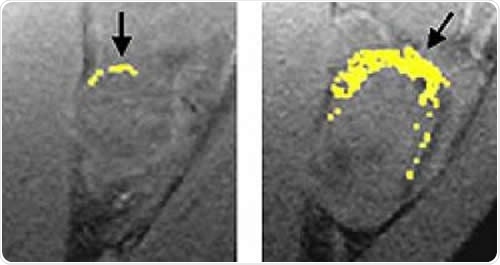

A tumor treated with fumagillin nanoparticles (left) is smaller than an untreated tumor. Nanoparticles containing an image-enhancing metal (yellow) show that the treated tumor has much less blood vessel growth than the untreated tumor. Image Credit: Washington University School of Medicine